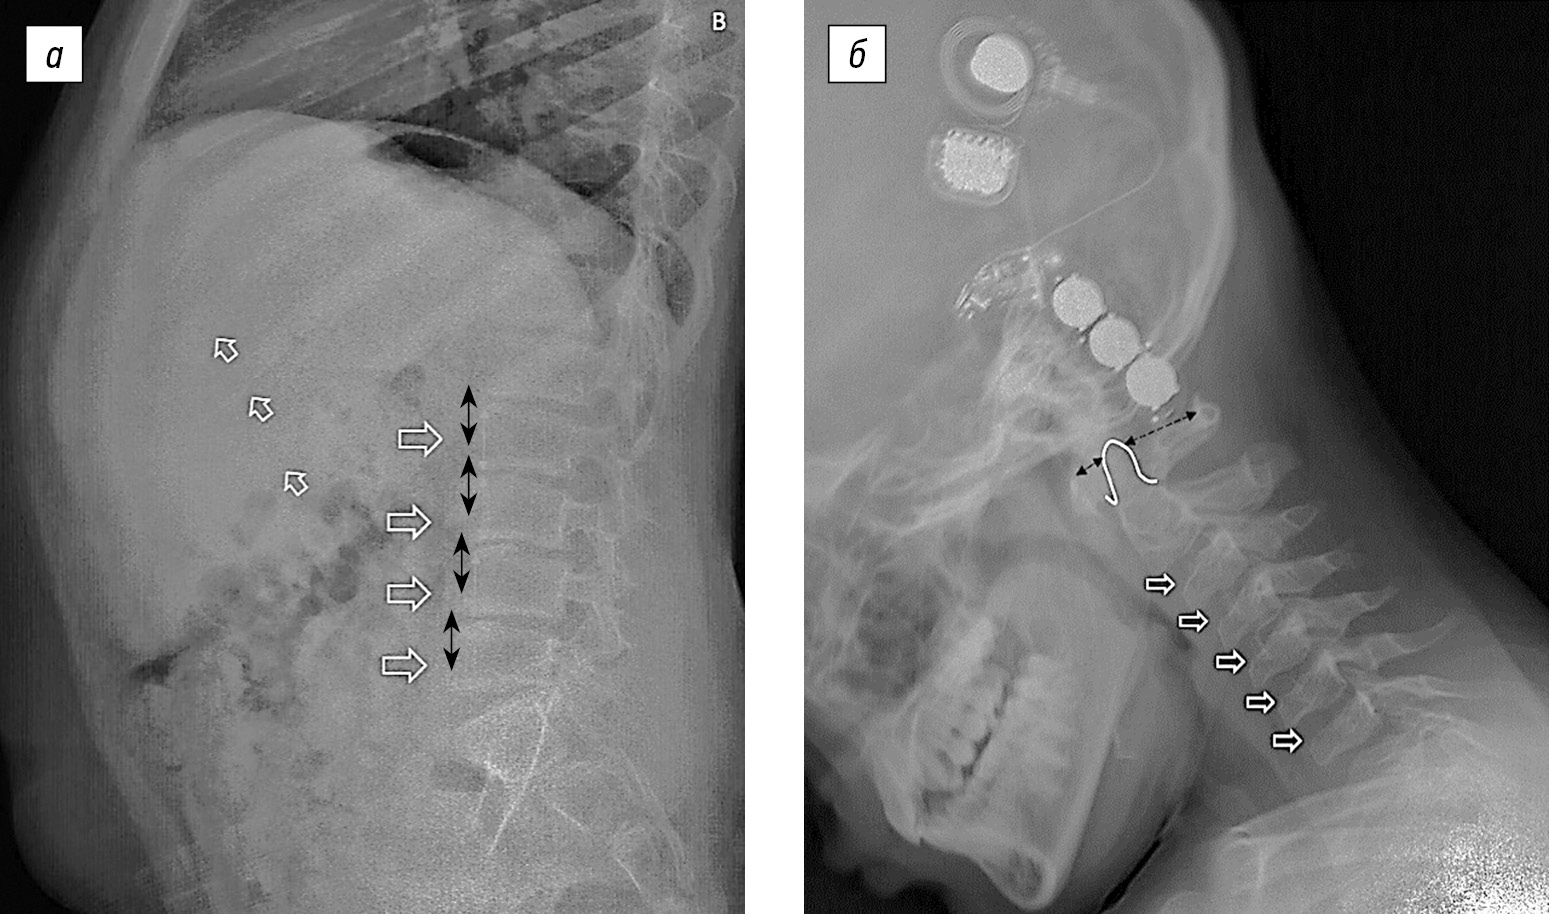

На боковой рентгенограмме в грудопоясничном отделе позвоночника отмечаются изменения формы тел позвонков по типу языковидной деформации, анизоспондилия, «весловидная» деформация ребер; в шейном отделе — гипоплазия зубовидного отростка II шейного позвонка, атланто-аксиальная нестабильность, деформация вентральных отделов шейных позвонков (рис. 2).

Рис. 2. Рентгенограммы шейного и грудного отдела позвоночника: а — белые стрелки — расширение межреберных промежутков, «весловидная» деформация ребер, деформация вентральных отделов позвонков; голубая пунктирная линия — анизоспондилия — неравномерность высоты позвонков в краниокаудальном направлении; б — белая линия — гипоплазия зубовидного отростка II шейного позвонка, черные стрелки — признаки атланто-аксиальной нестабильности, белые стрелки — деформация вентральных отделов шейных позвонков